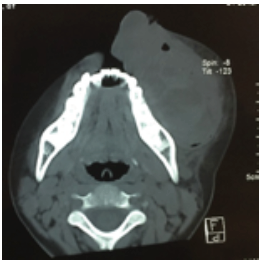

Paciente femenina de 8 años de edad, recibida en el mes de octubre de 2016, asintomática, sin antecedentes patológicos, alérgicos y quirúrgicos. Intraoralmente, presenta una masa tumoral de aproximadamente 6 x 6 cm a expensas de maxilar, que desplaza el primer molar y los molares temporales superiores izquierdos, no álgica a la manipulación (figura 1). En TAC contrastada se observa una lesión mixta de características osteolíticas, que involucra el seno maxilar, el reborde infraorbitario izquierdo y las celdillas etmoidales anteriores (figura 2, figura 3 y figura 4). Se realiza una biopsia incisional, obteniendo un diagnóstico de lesión central de células gigantes (figura 5). Se solicita estudio de niveles séricos de paratohormona y calcitonina, obteniéndose valores de laboratorios normales. Se inicia terapia esclerosante con triamcinolona, con aplicaciones semanales de 5ml de triamcinolona de 10mg con lidocaína 2% con epinefrina 1:100 000 UI (7). En enero de 2017, se presenta con dolor espontaneo e incremento exponencial de la lesión, causando deformidad hemifacial izquierda, obstruyendo en un 50 % la luz de la cavidad oral. Se interviene para escisión de lesión tumoral y curetaje, retirándose al 90% y se realiza además derivación de conducto parotídeo izquierdo. En marzo de 2017, acude a control con aumento de volumen intraoral nuevamente. Se informa a sus familiares sobre la existencia de otra terapéutica sustentada por diferentes publicaciones, para estas lesiones que no responden a los tratamientos con esteroides y a los quirúrgicos. Tras su aceptación se programa terapia antiangiogénica con interferón alfa 2ª vía subcutánea de 3 a 6 millones de UI semanales por 4 a 8 meses, iniciándolo a las 48h tras la cirugía (5). En abril, es reintervenida, sin complicaciones, para escisión quirúrgica de lesión central de células gigantes recidivante agresiva, y se inicia terapia con interferón alfa 2ª para reducción y esclerosis de tumor. Se solicita interconsulta a Servicio de Psicología a fin de mes, por datos de depresión. Se enfatiza esta relación con el medicamento, así como malestar general, astenia, somnolencia y afectación del estado general. El Servicio de Psicología diagnostica un estado depresivo leve, que no se considera indicativo para detener tratamiento con interferón alfa 2ª. En junio de 2017, se corrobora la esclerosis de la lesión a través de exploración con TAC de macizo facial, simple y contrastada. La paciente se encuentra sin datos de actividad tumoral, estado físico y psicológico en buenas condiciones, transcurridos 36 meses al día de hoy (figura 6 y figura 7).